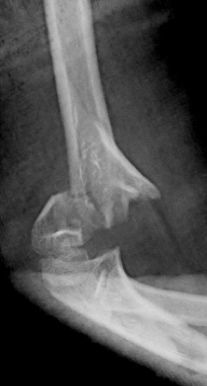

Figura 8: a-d, Imagen radiografica de fractura del cóndilo lateral con desplazamiento articular. Tratamiento quirúrgico mediante reducción abierta y osteosíntesis.